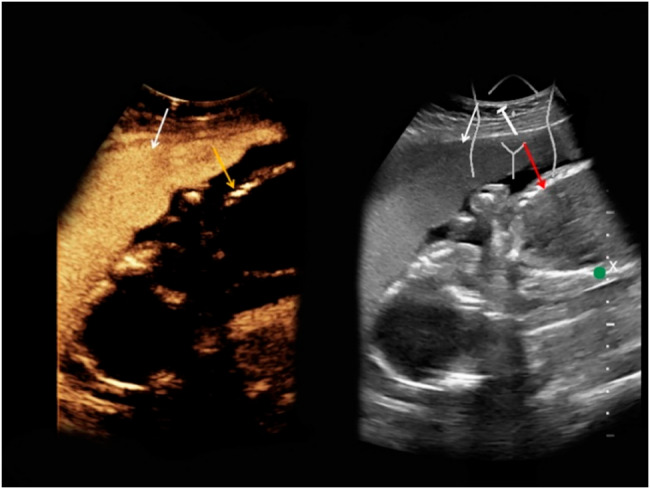

{"title":"Contrast-enhanced ultrasound for fetal and placental assessment: evidence, safety, and a roadmap for clinical translation.","authors":"Alushika Jain, Rajasbhala P Dhande, Pratapsingh H Parihar, Shivali Kashikar, Nishant Raj, Amit Toshniwal","doi":"10.1186/s13089-025-00449-x","DOIUrl":null,"url":null,"abstract":"<p><strong>Background: </strong>Fetal growth restriction (FGR), preeclampsia, and other placental disorders are leading contributors to perinatal morbidity and mortality, primarily due to impaired uteroplacental perfusion. Existing imaging modalities, such as Doppler ultrasound and fetal MRI, provide indirect or limited functional insights into placental and fetal perfusion, constraining timely clinical intervention.</p><p><strong>Objective: </strong>To evaluate contrast-enhanced ultrasound (CEUS) as a promising, safe, and real-time tool for assessing placental perfusion and its potential application in maternal-fetal medicine through comprehensive analysis of methodological parameters, safety profiles, and emerging computational techniques.</p><p><strong>Methods: </strong>A comprehensive synthesis of preclinical and clinical studies was conducted, focusing on the safety, efficacy, and current use of CEUS in pregnancy. Key findings were drawn from animal models (rats, sheep, macaques) and human studies involving 256 pregnant individuals, with detailed analysis of imaging protocols, contrast agent characteristics, and quantification methods.</p><p><strong>Results: </strong>CEUS utilizes intravascular microbubble contrast agents (1-8 μm diameter) that do not cross the placental barrier, enabling safe maternal imaging. However, size distribution analysis reveals sub-micron populations (8-20% by number) requiring careful evaluation. Preclinical models confirm CEUS ability to detect placental perfusion Changes with 54% reduction in perfusion index following uterine artery ligation (p < 0.001). Human studies demonstrate zero clinically significant adverse events among 256 cases, though critical gaps exist including absent biomarker monitoring and long-term follow-up. Emerging AI-enhanced analysis achieves 73-86% diagnostic accuracy using ensemble deep learning architectures. Current limitations include significant protocol heterogeneity (MI 0.05-0.19, frequency 2-9 MHz) and absence of standardization.</p><p><strong>Conclusion: </strong>CEUS presents a compelling solution for perfusion imaging in pregnancy, offering functional, bedside imaging without fetal exposure to contrast agents. However, methodological limitations, knowledge gaps regarding long-term outcomes, and the distinction between conventional microbubbles and emerging nanobubble formulations demand systematic research investment. Clinical translation requires standardized protocols, comprehensive safety monitoring including biomarker assessment, ethical oversight, and long-term outcome studies to support integration into routine obstetric care.</p>","PeriodicalId":36911,"journal":{"name":"Ultrasound Journal","volume":"17 1","pages":"43"},"PeriodicalIF":2.9000,"publicationDate":"2025-10-06","publicationTypes":"Journal Article","fieldsOfStudy":null,"isOpenAccess":false,"openAccessPdf":"https://www.ncbi.nlm.nih.gov/pmc/articles/PMC12501096/pdf/","citationCount":"0","resultStr":null,"platform":"Semanticscholar","paperid":null,"PeriodicalName":"Ultrasound Journal","FirstCategoryId":"1085","ListUrlMain":"https://doi.org/10.1186/s13089-025-00449-x","RegionNum":0,"RegionCategory":null,"ArticlePicture":[],"TitleCN":null,"AbstractTextCN":null,"PMCID":null,"EPubDate":"","PubModel":"","JCR":"Q2","JCRName":"Medicine","Score":null,"Total":0}

Results: CEUS utilizes intravascular microbubble contrast agents (1-8 μm diameter) that do not cross the placental barrier, enabling safe maternal imaging. However, size distribution analysis reveals sub-micron populations (8-20% by number) requiring careful evaluation. Preclinical models confirm CEUS ability to detect placental perfusion Changes with 54% reduction in perfusion index following uterine artery ligation (p < 0.001). Human studies demonstrate zero clinically significant adverse events among 256 cases, though critical gaps exist including absent biomarker monitoring and long-term follow-up. Emerging AI-enhanced analysis achieves 73-86% diagnostic accuracy using ensemble deep learning architectures. Current limitations include significant protocol heterogeneity (MI 0.05-0.19, frequency 2-9 MHz) and absence of standardization.